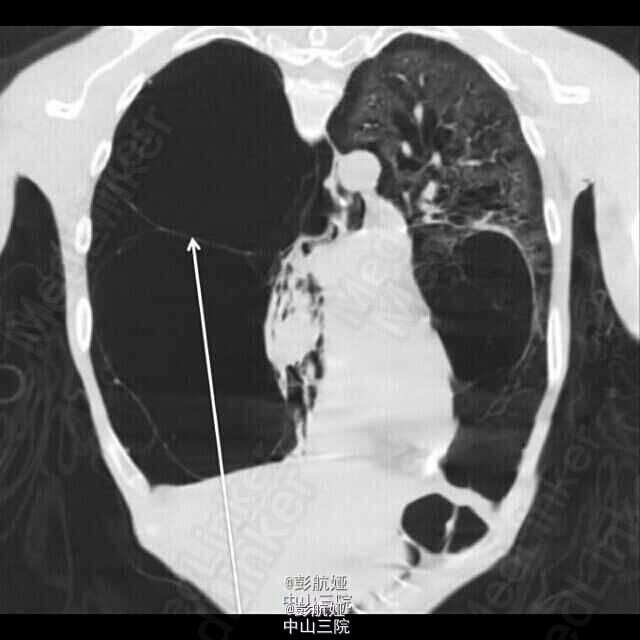

给予高流量吸氧、硫酸舒喘灵喷雾剂、异丙托铵、静脉注射甲强龙、抗生素、管状胸廓造口术后病情逐渐平稳,并行CT检查,提示右肺因肺大疱及支气管扩张已完全萎缩,右肺的气液平考虑双重感染并伴有分泌物,未见气胸,患者入呼吸科后继续抗感染及激素治疗,并至专科医院行肺移植。

鉴别肺大疱与气胸是十分重要的,肺大疱的患者气胸风险增加,普通胸片检查没有CT敏感,但患者病情通常无法平稳至可行CT检查;肺部的超声检查此时可作为一项可靠地诊断方法,肺部滑行线的出现可以排除气胸,而肺点出现时就可以考虑合并气胸。